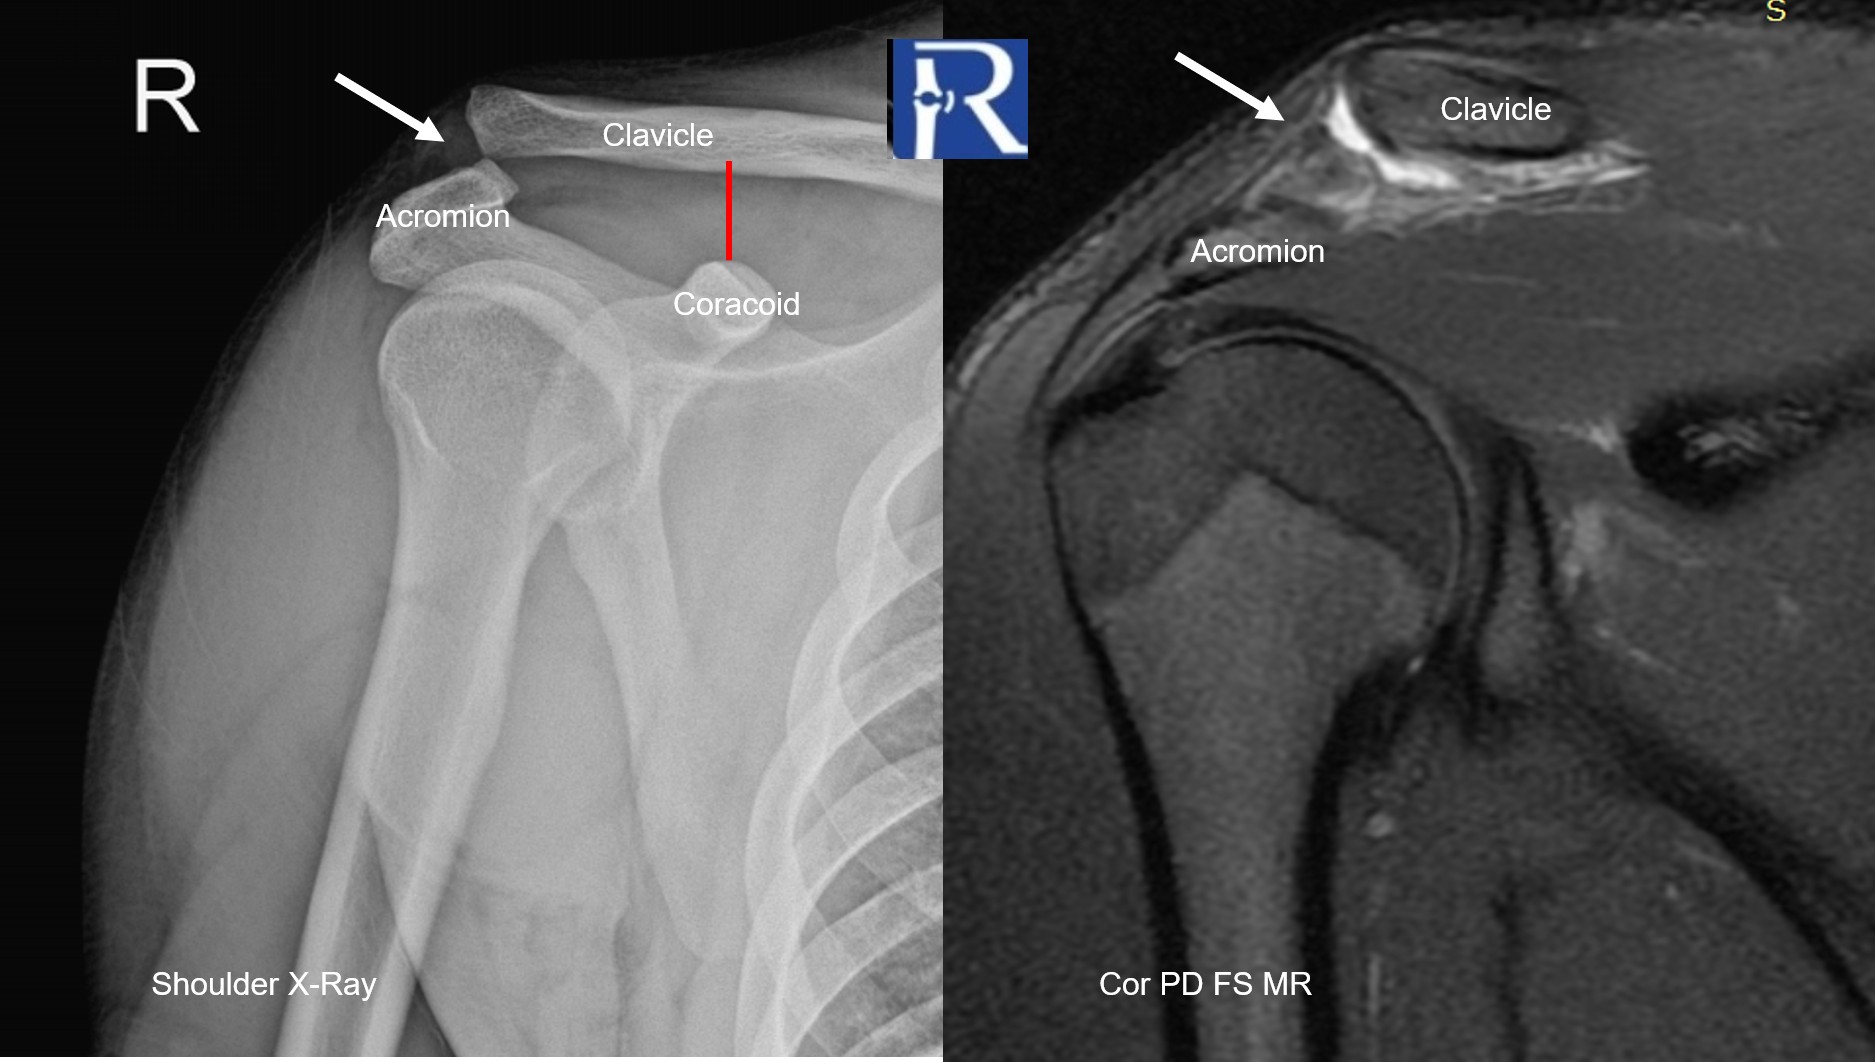

Clinical Presentation A 20-year-old male presented with pain and swelling over the superior aspect of the right shoulder following a motorcycle acc ...

Mehmet Fatih Tumer, MD, and Ozgur Tosun, MD Department of Radiology, Izmir Katip Celebi University, Ataturk Training and Research Hospital, Izmir/T ...